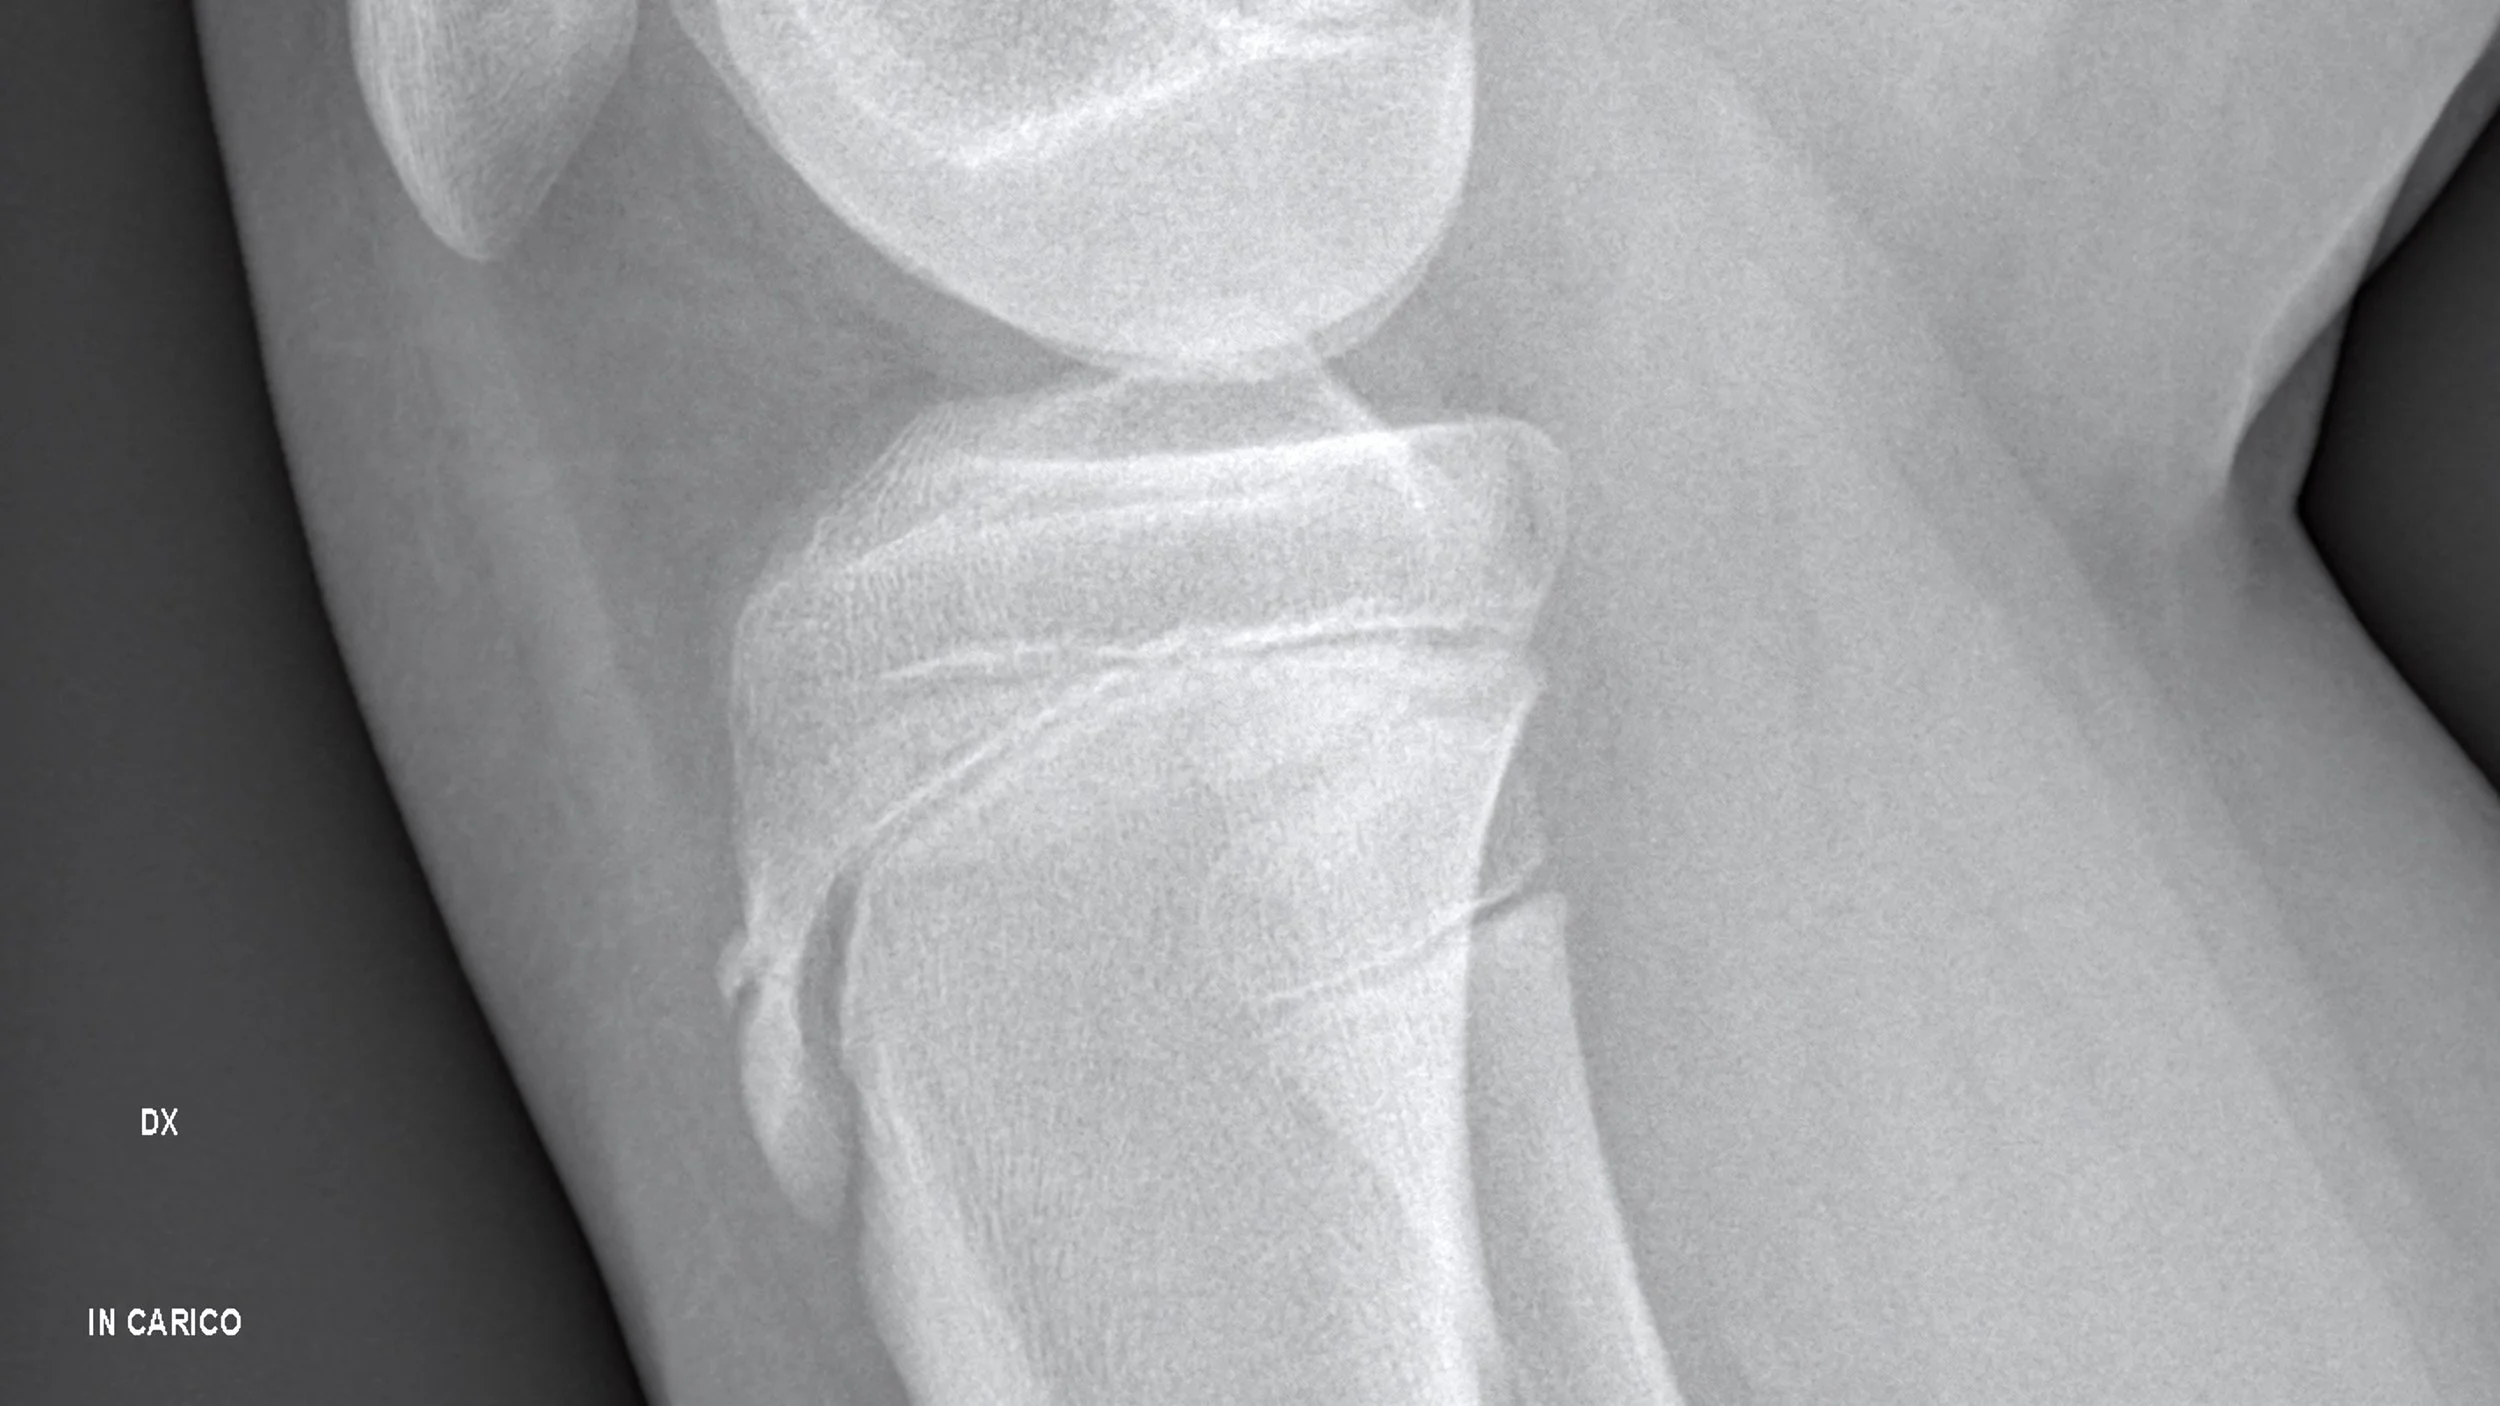

Knee Pain and Patellar Tracking Disorder

Knee pain can make everyday activities like walking, climbing stairs, or standing up difficult. One common cause of knee pain relief issues is patellar tracking disorder (PTD), a condition where the kneecap (patella misalignment treatment) moves out of its normal alignment when bending or straightening the knee.

Runner’s Knee: How Gonstead Chiropractic Helps Sarasota Runners Get Back on Track

Runner’s Knee — or patellofemoral pain syndrome — is one of the most common causes of knee pain among Sarasota runners. At Vertical Chiropractic® Sarasota, we use Gonstead extremity chiropractic care to restore alignment, improve biomechanics, and help runners recover naturally without drugs or surgery. Whether you’re training on Siesta Key Beach or running the Legacy Trail, discover how specific chiropractic adjustments can get you back on track faster and stronger.